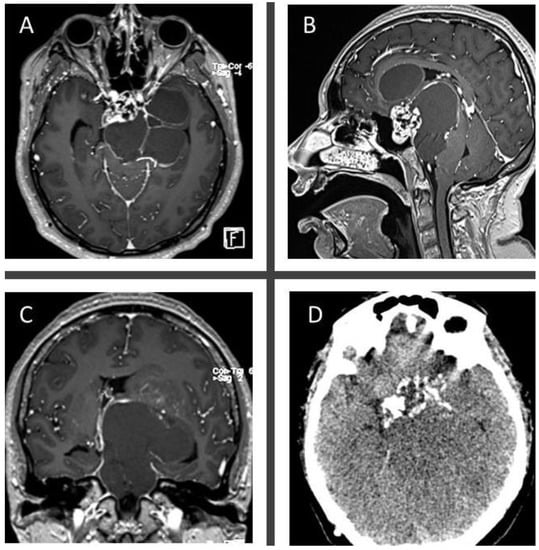

3.2.3. Case 3